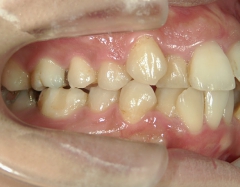

矯正歯科 治療後矯正歯科 全顎ワイヤー矯正 治療後矯正歯科(全顎ワイヤー矯正)治療後

矯正歯科 治療後

no.31_1962_治療後_右.JPGno.31_1962_治療後_正面.JPGno.31_1962_治療後_左.JPG